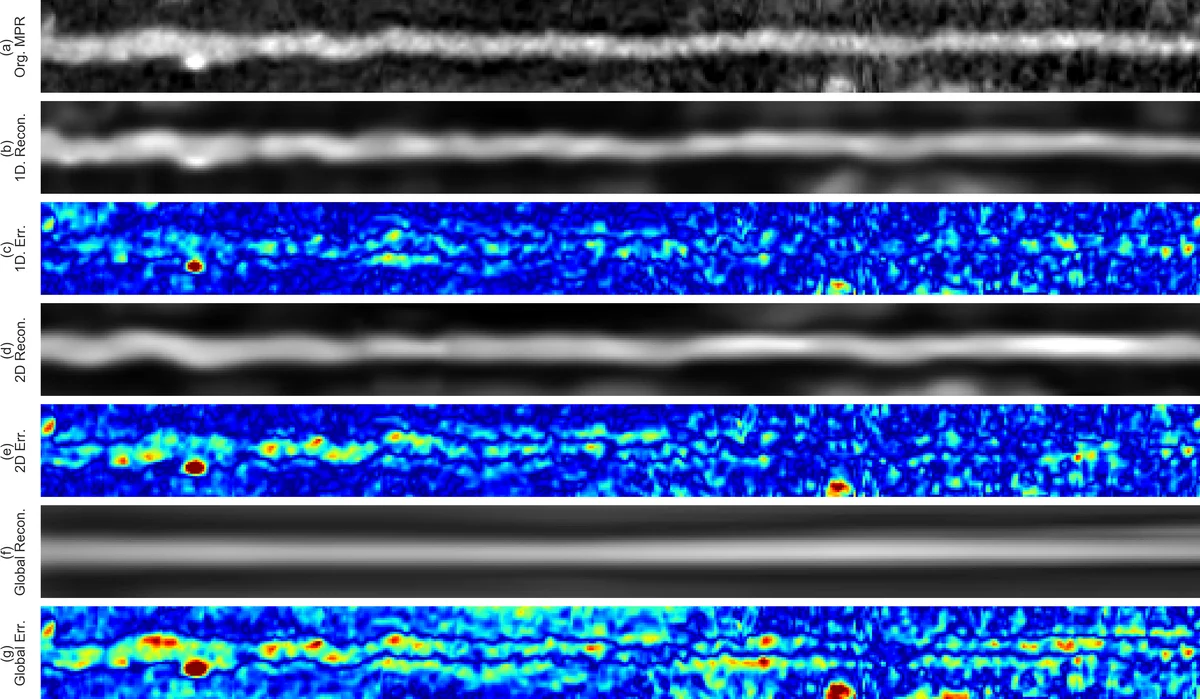

이 논문은 관상동맥 질환 환자에서 기능적으로 의미 있는 협착을 판단하기 위해, 기존의 혈류 시뮬레이션 기반 FFR 추정 방법이 요구하는 정확한 혈관 내강 분할의 어려움을 회피한다. 대신, 자동으로 추출된 관 중심선을 이용해 직선화된 다평면 재구성(MPR) 볼륨을 생성하고, 두 단계의 비지도 학습 자동인코더(3D‑VCAE와 1D‑CAE)로 고차원 영상을 고정 길이 잠재 벡터로 압축한다. 3D‑VCAE는 관을 일정 길이의 서브볼륨으로 나누어 공간적 특징을 추출하고, 1D‑CAE는 이러한 서브볼륨 인코딩을 순차적으로 처리해 전체 길이에 무관한 시퀀스 표현을 만든다. 이렇게 얻은 잠재 벡터는 차원이 낮고, 노이즈와 해부학적 변이를 어느 정도 억제한다. 이후 선형 SVM을 이용해 “FFR < 0.80”인 관을 양성으로 분류한다.